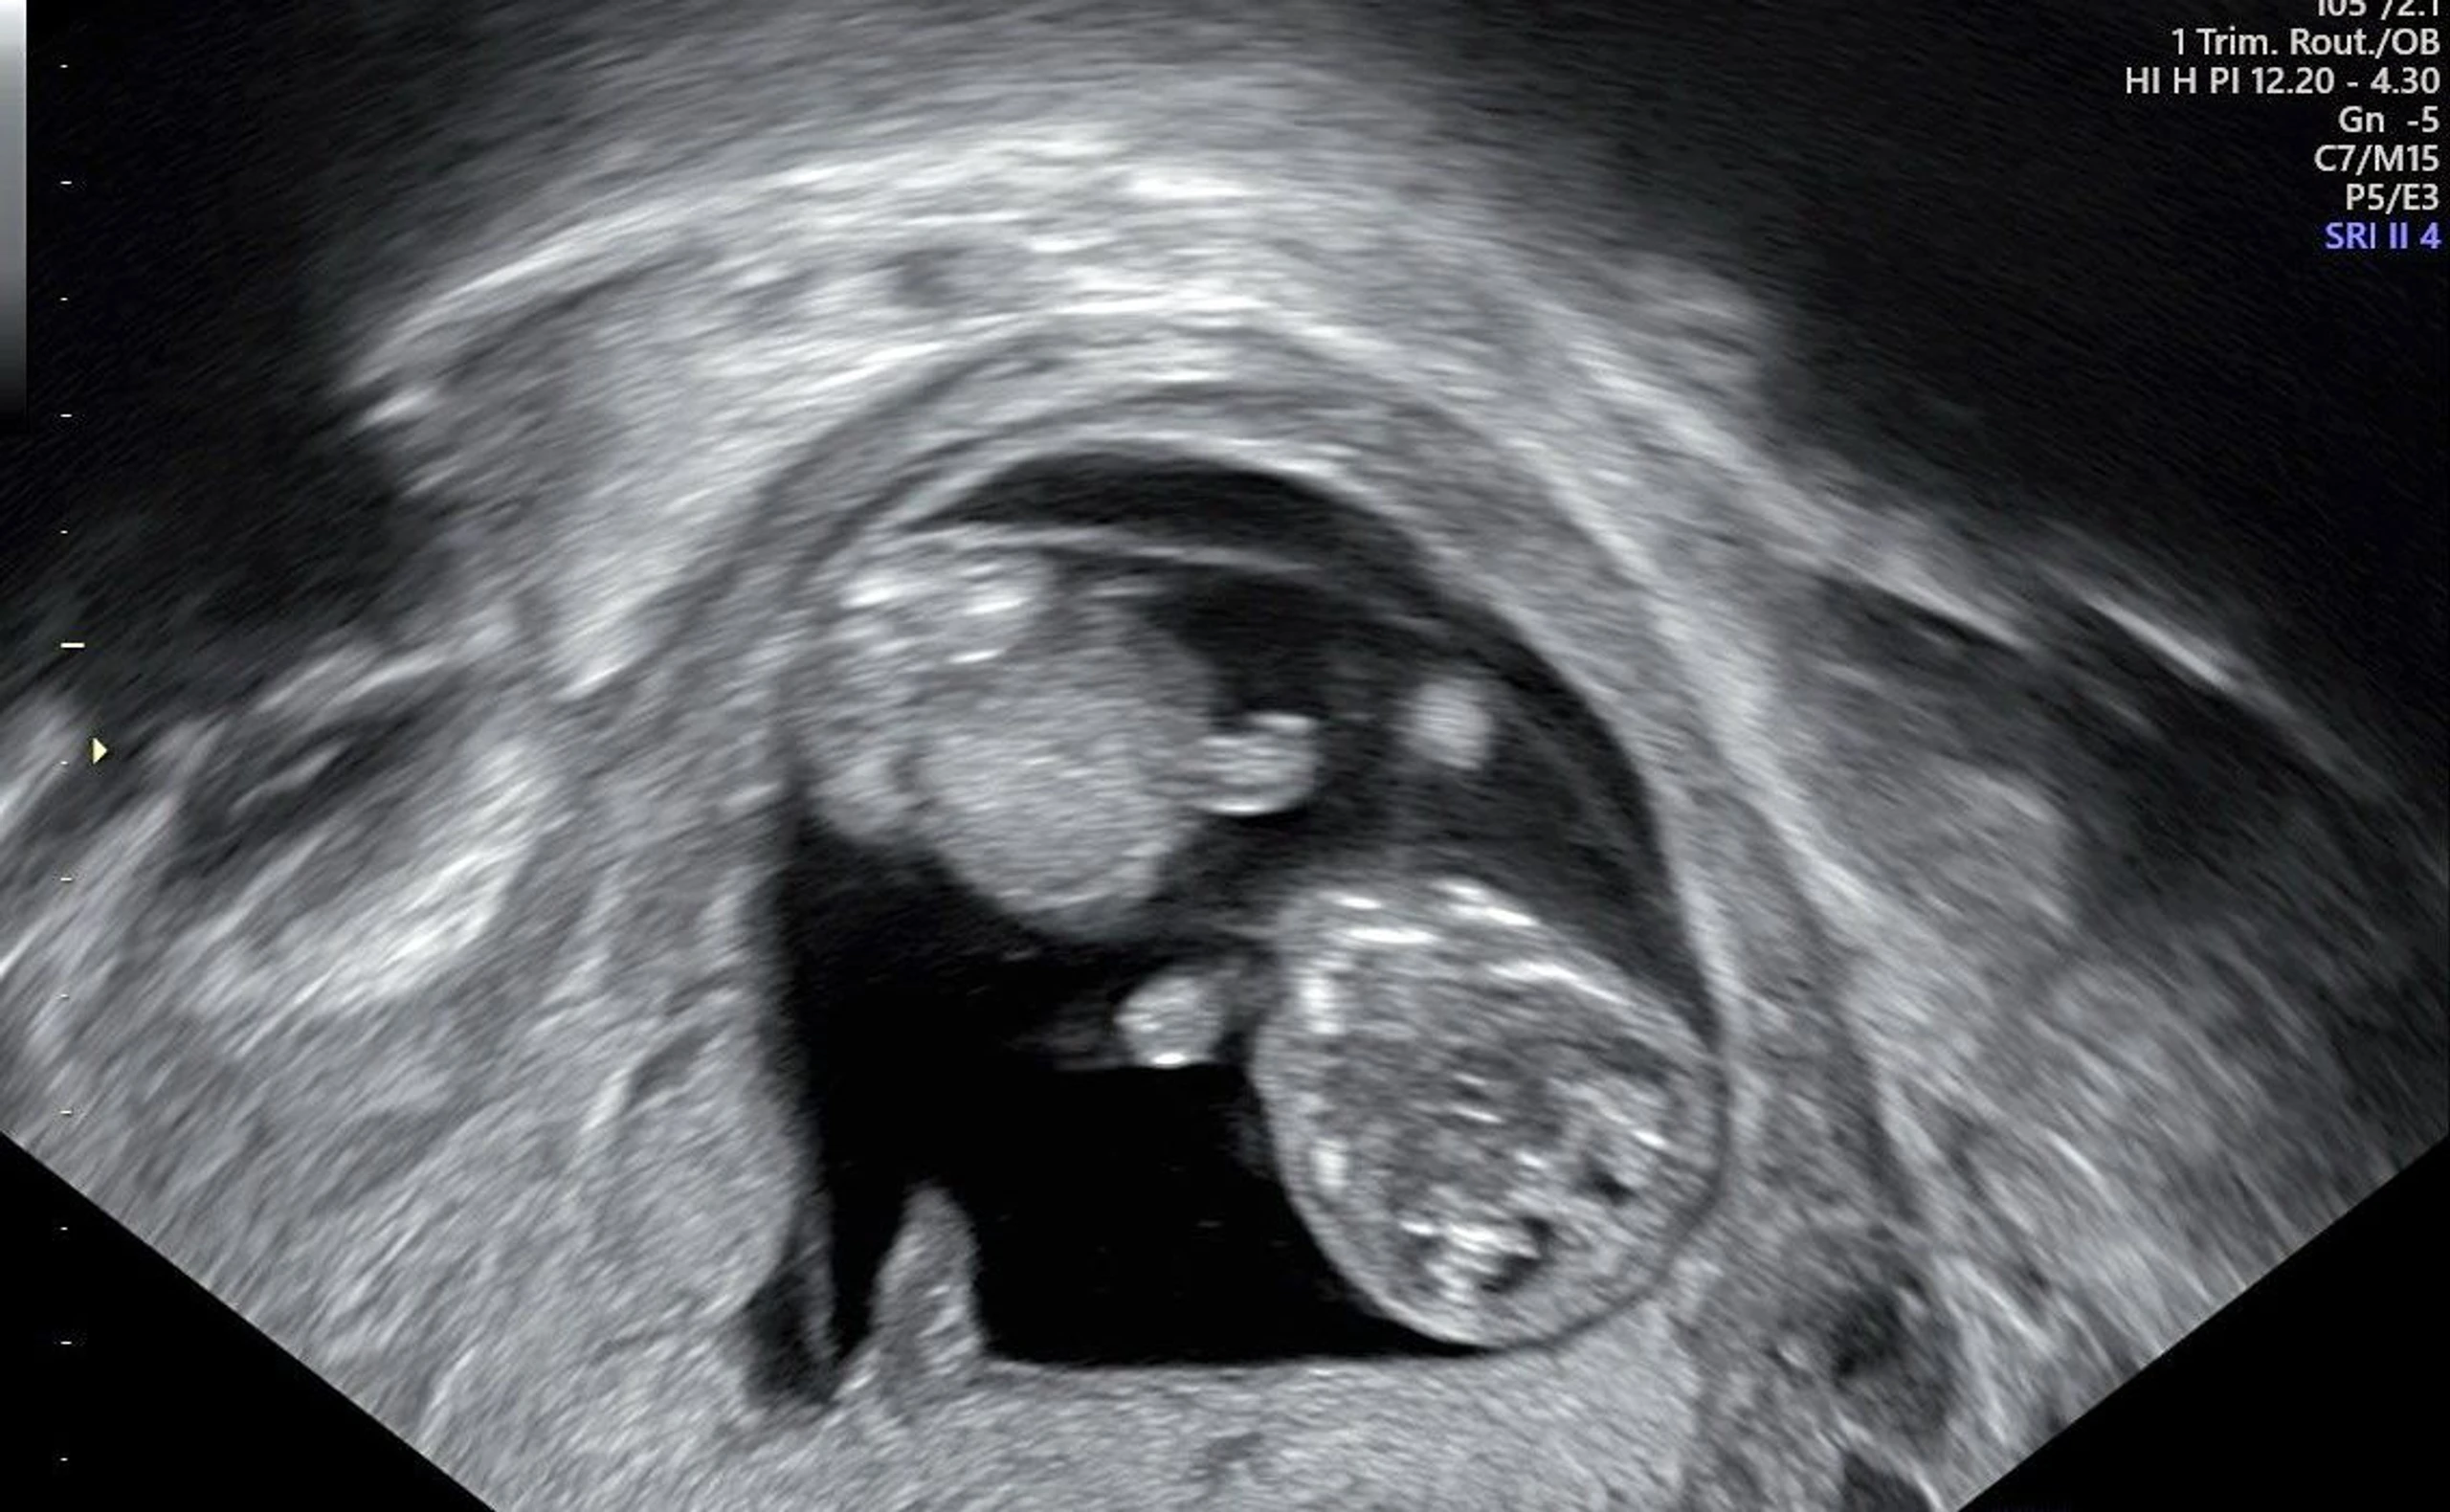

Schwangerschaftswochen: So verläuft eine Schwangerschaft

Woche für Woche zum Wunder: Wie verlaufen die einzelnen Schwangerschaftswochen, wie viele gibt es eigentlich und wie entwickelt si...